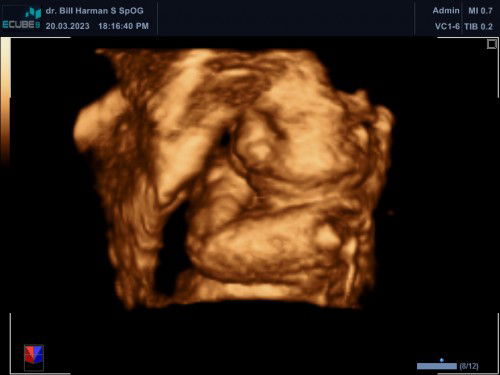

27 weeks 3Day usg 4D

Hii aunty semua🥰Hpl juni alhamdulillah sehat dan normal semua debay nya jenis kelamin Cowok ,Bbj 1071grm.waktu usg debay nya lagi santuy tangan nya lucu miring gitu😍